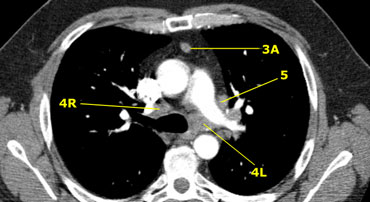

Axial CT anatomy

Images by Dr. Aurelia Fairise of the Institut de Cancérologie de Lorraine in Nancy.

3A. Trước mạch máu

4R. Cạnh dưới phải khí quản

4L. Cạnh dưới trái khí quản

5. Dưới quai động mạch chủ

Hạch ở phía trước mạch máu – 3A (mũi tên)

Hạch ở nhóm 4R, và cũng có hạch ở bên quai động mạch chủ (nhóm 6)

Hình ảnh ở mức trên của thân động mạch phổi cho thấy hạch cạnh dưới khí quản bên phải và bên trái. Cũng có hạch nhóm 3 và nhóm 5.

Hình ảnh ở ngang mức thấp của khí quản, trên góc carina.

Hạch nhóm 4L, nằm giữa thân động mạch phổi và động mạch chủ nhưng không thuộc cửa sổ phế chủ do chúng nằm ở giữa của dây chằng động mạch.

Hạch ở phía bên của thân động mạch phổi thuộc nhóm 5.